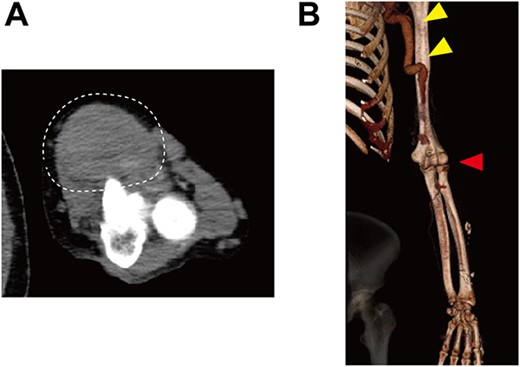

Upon admission, the patient received immunosuppressive treatment with prednisolone (5 mg/day), tacrolimus (1.5 mg/day) and everolimus (0.5 mg/day) for renal transplantation. A physical examination revealed a hard mass in the left antecubital fossa of the volar aspect (Fig. 1), and contrast computed tomography (CT) showed a true brachial aneurysm measuring 32 × 42 mm in diameter at the anterior aspect of the elbow joint (Fig. 2A). In addition, the brachial artery in the proximal site of the aneurysm was dilated to 15 mm in diameter (Fig. 2B). Although the aneurysm and radial artery were completely obstructed with a thrombus, the ulnar artery was enhanced with blood supply from a collateral artery. These findings suggested that the pain and cyanosis symptoms were caused by ischemia or distal embolism.

Preoperative contrast CT showing (A) a true brachial aneurysm at the anterior aspect of the elbow joint, which was obstructed by a thrombus (white dashed circle), and (B) the dilated brachial artery (yellow arrows). Red arrow indicates the level of the true brachial aneurysm.